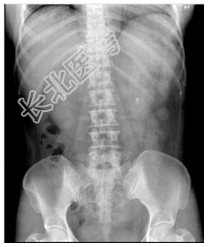

- [材料题] 患者,女性,50岁。腰痛1个月。查体:心、肺(-),腹平软,无压痛,腰部叩击痛。行腰椎正侧位检查。

- 简答题1、患者的诊断及依据是什么?

- 简答题2、鉴别诊断有哪些?